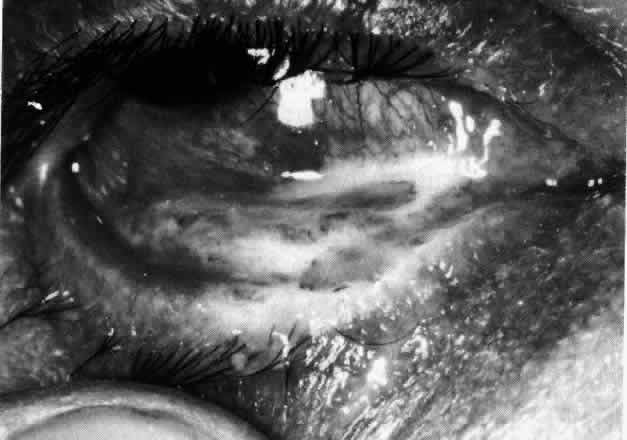

The sclera that is edematous is pushed forward, and the deep episcleral network is more congested than the superficial networks (Figs. 27 and 28). It is usually easy to ascertain by simple observation that the patient has scleritis and not episcleritis. However, it is not as easy to ascertain whether the patient has early necrotizing scleritis. It is in these patients that fluorescein angiography has considerable value, because the first changes are detectable in the ocular vasculature. Prompt and adequate treatment can prevent these changes from becoming irreversible.

Fig. 27. In scleritis, maximum congestion occurs in deep episcleral plexus, which is bowed forward by underlying scleral edema. Episcleral tissue is slightly infiltrated and superficial plexus is slightly congested (see Fig. 14). (Watson PG, Hayreh S, Awdry P: Episcleritis and scleritis. Br J Ophthalmol 52:278–279, 1968)

Fig. 28. Nodular scleritis. Both the anterior conjunctival slit and the deep scleral slit are displaced forward by the scleral edema. There is little separation between these two beams, indicating that all the edema is in the sclera and not in the overlying episclera. (Watson PG, Hayreh S, Awdry P: Episcleritis and scleritis. Br J Ophthalmol 52:278–279, 1968)